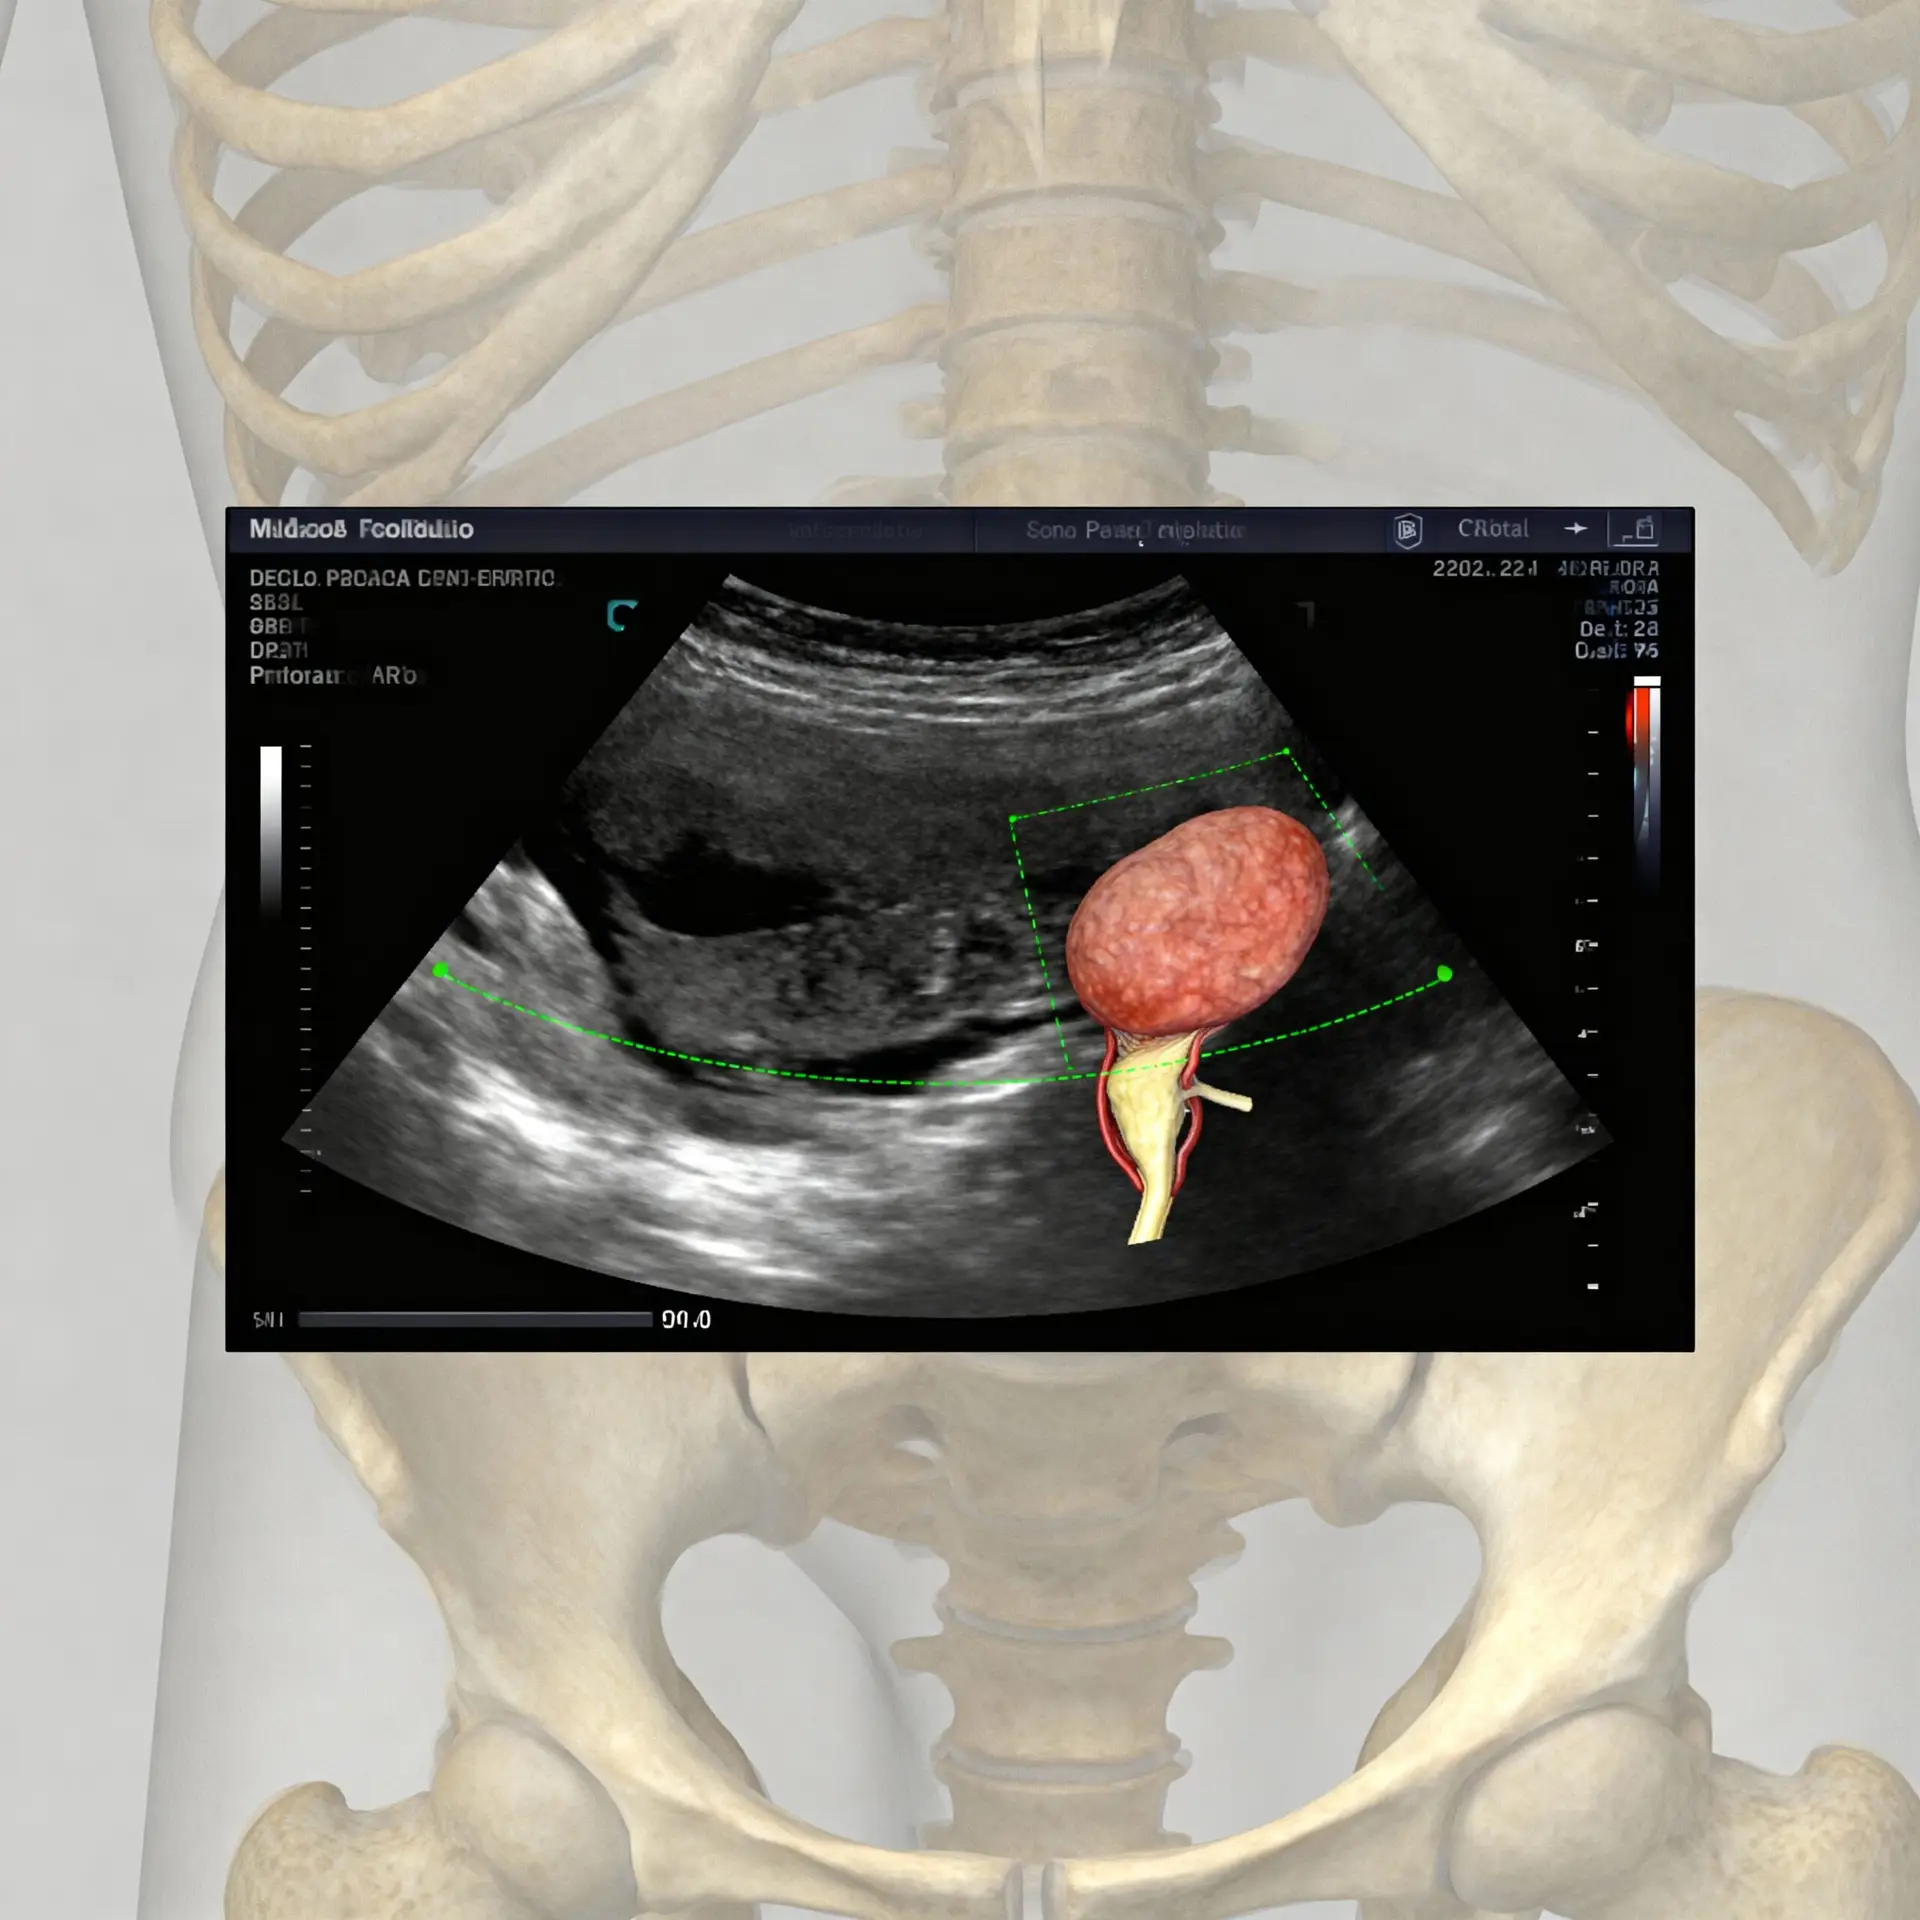

Con l’avanzare dell’età , il tessuto prostatico è soggetto a cambiamenti fisiologici. L’ingrossamento è quasi inevitabile, ma la velocità e l’entità di questo processo variano da individuo a individuo. Ed è qui che la tecnologia diagnostica interviene. L’utilizzo dell’ecografo prostata (nella sua variante addominale o transrettale) offre al medico specialista, l’urologo, la possibilità di visualizzare la ghiandola, misurarne il volume, valutarne la struttura interna e individuare eventuali anomalie o calcificazioni. Capire l’anatomia della prostata è il primo passo per apprezzare perché l’esame ecografico è diventato l’esame di riferimento per il controllo periodico.

Affrontare i problemi prostatici non significa solo curare, ma soprattutto prevenire. Il motivo principale per cui l’ecografo prostata è diventato uno strumento diagnostico essenziale è la sua capacità di fornire un quadro visivo immediato e dettagliato dello stato di salute della ghiandola senza ricorrere a radiazioni o procedure dolorose. Questo esame, eseguito con competenza da un radiologo o un urologo, offre informazioni cruciali che non possono essere ottenute con la sola anamnesi o l’esame del sangue (come il PSA).

- Beneficio 1: Misurazione Accurata del Volume Prostatico: L’ecografia permette di calcolare con precisione le dimensioni della prostata. Un volume elevato (oltre i 30-40 cc) è il principale indicatore dell’Ipertrofia Prostatica Benigna (IPB). Conoscere questo dato è fondamentale per stabilire la strategia terapeutica, che sia di semplice osservazione, farmacologica o, in rari casi, chirurgica.

- Beneficio 2: Valutazione della Struttura e Omogeneità della Ghiandola: L’esame non si limita a misurare, ma analizza l’architettura interna. Permette di identificare calcificazioni, aree ipo-ecogene (potenziali segni di malignità che richiedono approfondimento) o l’eventuale presenza di noduli. Questo livello di dettaglio è irraggiungibile con altri metodi di screening di prima linea.

- Beneficio 3: Determinazione del Residuo Post-Minzionale (RPM): Uno degli aspetti più importanti e pratici dell’ecografia è la possibilità di misurare la quantità di urina che rimane nella vescica dopo aver urinato. Un alto RPM indica che la prostata ingrossata sta ostacolando lo svuotamento vescicale, un fattore che aumenta il rischio di infezioni urinarie e, a lungo termine, può danneggiare i reni.

- Beneficio 4: Guida per Procedure Più Specifiche: Nei casi in cui i valori del PSA siano elevati o vengano riscontrate anomalie strutturali, l’ecografo prostata transrettale (EAT) è spesso utilizzato come guida visiva per eseguire una biopsia mirata. In sintesi, è la mappa che indirizza il medico nel punto esatto dove prelevare un campione, aumentando l’affidabilità diagnostica.